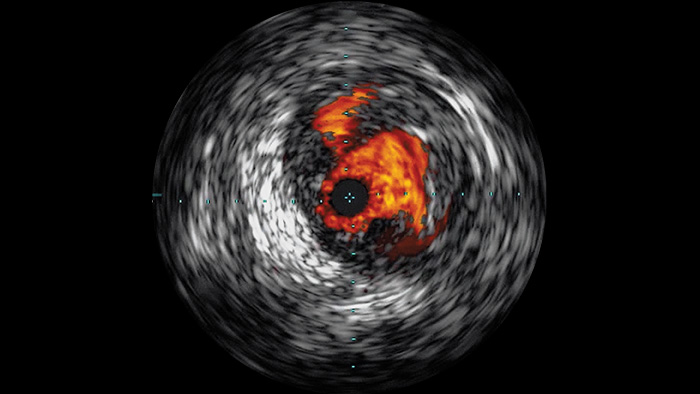

Ecografía intravascular (EIV) mejora la evaluación de la enfermedad

Ecografía intravascular

La ecografía intravascular (EIV) es una tecnología de imágenes basada en catéteres que permite a los médicos visualizar los vasos sanguíneos de adentro hacia afuera para ayudar a evaluar la presencia y el alcance de la enfermedad. La EIV ayuda a decidir, guiar y confirmar el tratamiento intervencionista adecuado para cada paciente.